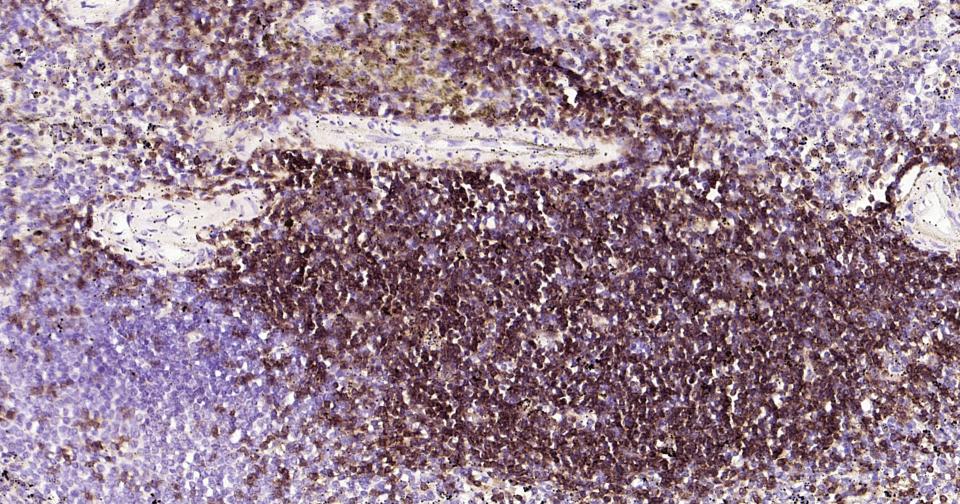

| IHC-P | Human | 1:100-500 | |